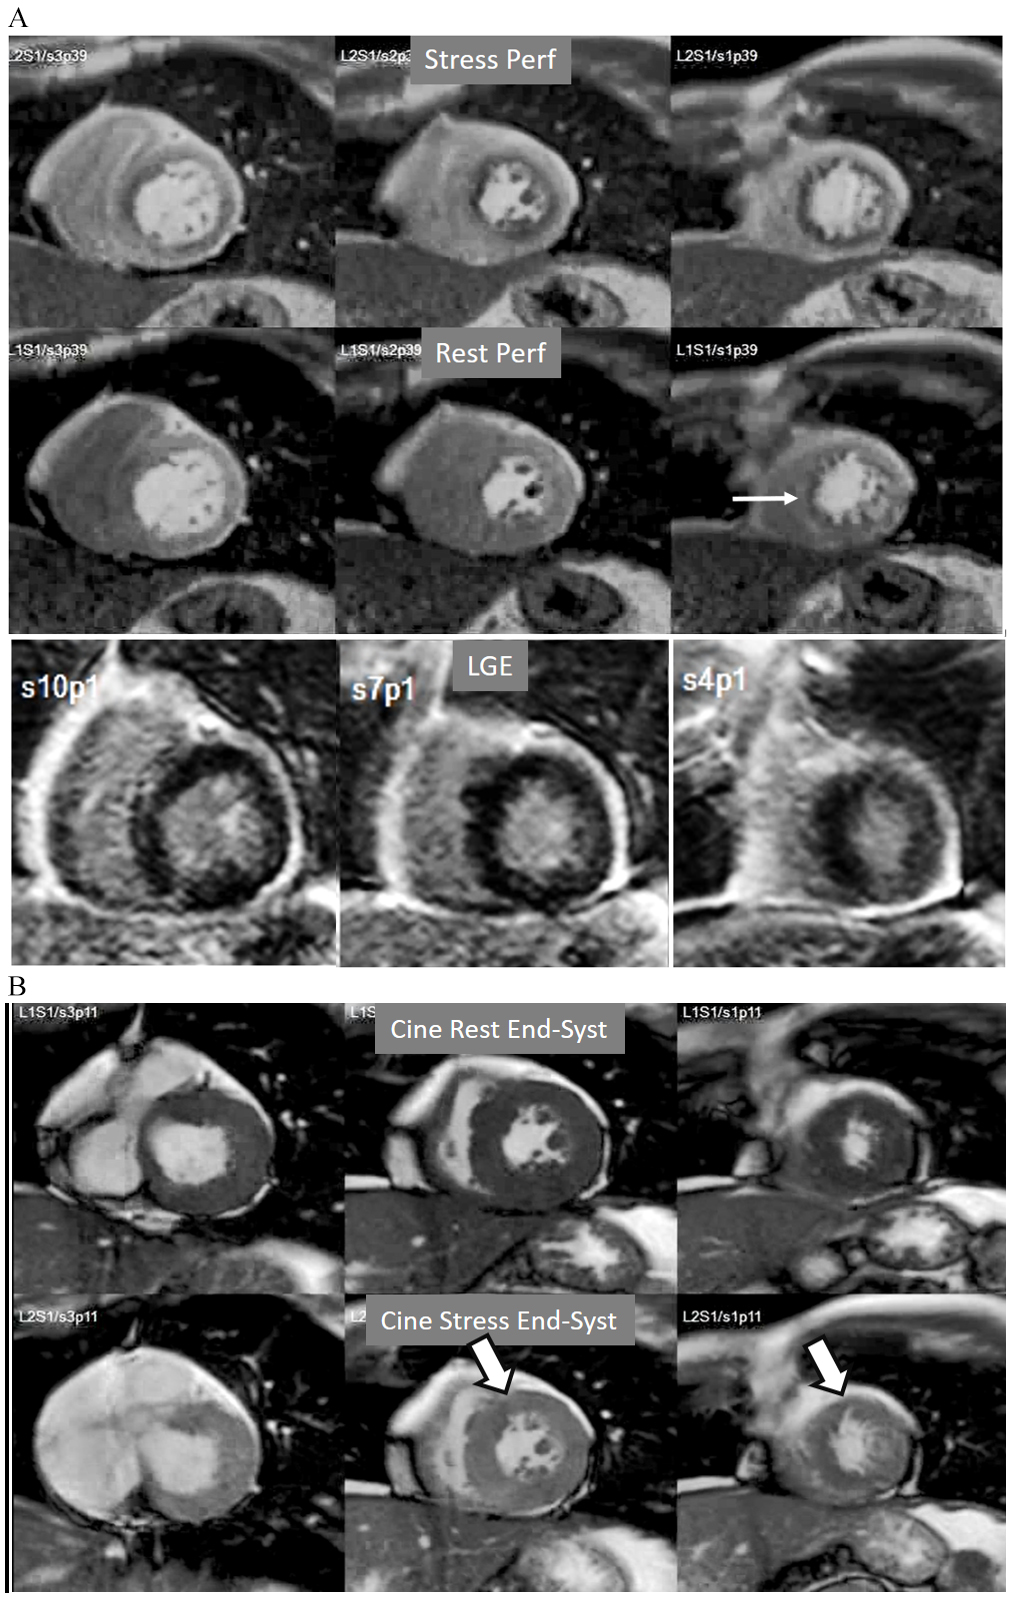

A not infrequent finding is a diffuse, annular, transient, subendocardial defect not present at rest (Fig. 9), which, in the absence of any recognizable obstructive lesion in an epicardial coronary artery, has been deemed to correspond to diffuse microvascular dysfunction (MVD) [41, 42]. CMR perfusion is sensitive to both the downstream effects of discrete epicardial stenoses and those due to disturbances of coronary microcirculation, and subendocardial hypoperfusion is on the pathophysiological basis of each one. For this reason, theoretically, a global, inducible subendocardial defect, could also be due to multivessel epicardial disease with balanced ischemia. In practice, however, this latter instance presents with extensive but heterogenous defects in terms of intensity, persistence and transmurality and, not rarely, also with perfusion defects at rest (Fig. 10A). Importantly, an accompanying induced contractile disfunction may be found in particularly impaired regions (Fig. 10B), a finding which is never seen in MVD.

Fig. 10.Multi-vessel perfusion defect. (A) Global stress hypoperfusion in a patient with multivessel CAD. Observe the non-uniformity of the defect, with different degrees of intensity and transmurality and, also, with the presence of a defect at rest (arrow), in the absence of LGE. (B) End-systolic frames from cine studies at the same level of the perfusion slices showing inducible antero-septal hypokinesia during stress (arrows).

A study exploring further components of perfusion defects [36] showed that, besides extension and transmurality, also the presence of inducible contractile defect and, particularly, persistence of the defect throughout the full duration of the sequence, were also related with an adverse prognosis (Fig. 21). High values of an ischemic burden score based on these parameters showed prognostic value for clinical improvement after PCI in patients with chronic total coronary occlusion [48].

Fig. 21.Grading perfusion defects. The upper 2 panels present with the very last frames of perfusion studies where a persistent defect is seen at stress in the infero-lateral and antero-septal regions (asterisks). The lower 2 panels show corresponding end-systolic frames with conspicuous contractile adenosine-induced defects (arrows) in both regions.